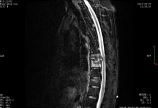

患者男,59岁,因“胸背部疼痛2月余”入院。2月前无明显诱因出现胸背部疼痛,呈酸胀痛,无放射,直立行走后加重,无明显缓解体位。无明显发热、乏力盗汗、双下肢功能障碍、大小便困难等症状。曾至当地医院诊疗,行胸椎MRI提示胸椎结核并椎旁脓肿形成,为求进一步治疗来我院。患者自发病以来精神、饮食、睡眠尚可,二便正常,体重无明显变化。既往陈旧性肺结核病史。查体胸8-10节段棘突间及椎旁压痛及叩击痛阳性。    胸椎CT及MRI提示:胸8、9椎体、椎间隙破坏并椎旁软组织肿胀,考虑椎体结核。B超示:双侧腰大肌未见明显异常,腹腔内未探及明显液暗区声像。血象不高,血沉54mm/h,c反应蛋白 12.6。PPD弱阳性,抗结核抗体及斑点试验阴性。肿瘤相关检查未见明显异常。综合各项临床资料后初步诊断:胸椎病变查因:结核可能性大。遂予试验性四联抗结核治疗3周,复查血沉36mm/h。术前准备妥当后,在全麻下行胸椎后路病灶清除减压植骨内固定+病理活检术,术中未见明显脓肿及干酪样病灶,彻底清除病灶后局部应用链霉素。    术后病理结果回示:纤维组织增生变性,灶状钙化,较多炎性细胞浸润,倾向炎性增生。细菌培养结果回示:阴沟肠杆菌。修正诊断为:阴沟肠杆菌性胸椎骨髓炎。停止抗结核治疗,据药敏使用美罗培南静脉抗感染治疗。术后患者疼痛症状无缓解,且合并低热,引流量持续不减,逐渐变稀薄浑浊,考虑局部感染未控制,再次于全麻下行胸椎后路病灶清除灌洗引流术。术中见感染已蔓延至椎管内,美罗培南稀释后彻底冲洗切口,放置灌洗引流装置持续灌洗,术后2周直至无明显炎性渗液流出后拔除。静脉应用美罗培南满9周,复查血沉及c反应蛋白正常后停药。经过上述处理,患者胸背部疼痛症状逐渐缓解,复查CT及MRI提示内固定器位置良好,胸椎局部病灶情况控制可,遂痊愈出院。    总结:阴沟肠杆菌所致椎体骨髓炎在临床少见,易与椎体结核混淆,彻底的局部病灶清除及足够疗程的合理抗感染治疗是关键。